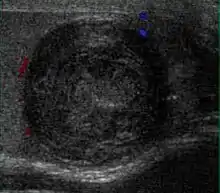

Patients with testicular lymphoma are usually old aged around 60 years of age, present with painless testicular enlargement and less commonly with other systemic symptoms such as weight loss, anorexia, fever and weakness. Bilateral testicle involvements are common and occur in 8.5% to 18% of cases. At sonography, most lymphomas are homogeneous and diffusely replace the testis [Fig. 7]. However focal hypoechoic lesions can occur, hemorrhage and necrosis are rare. At times, the sonographic appearance of lymphoma is indistinguishable from that of the germ cell tumors [Fig. 8], then the patient's age at presentation, symptoms, and medical history, as well as multiplicity and bilaterality of the lesions, are all important factors in making the appropriate diagnosis.